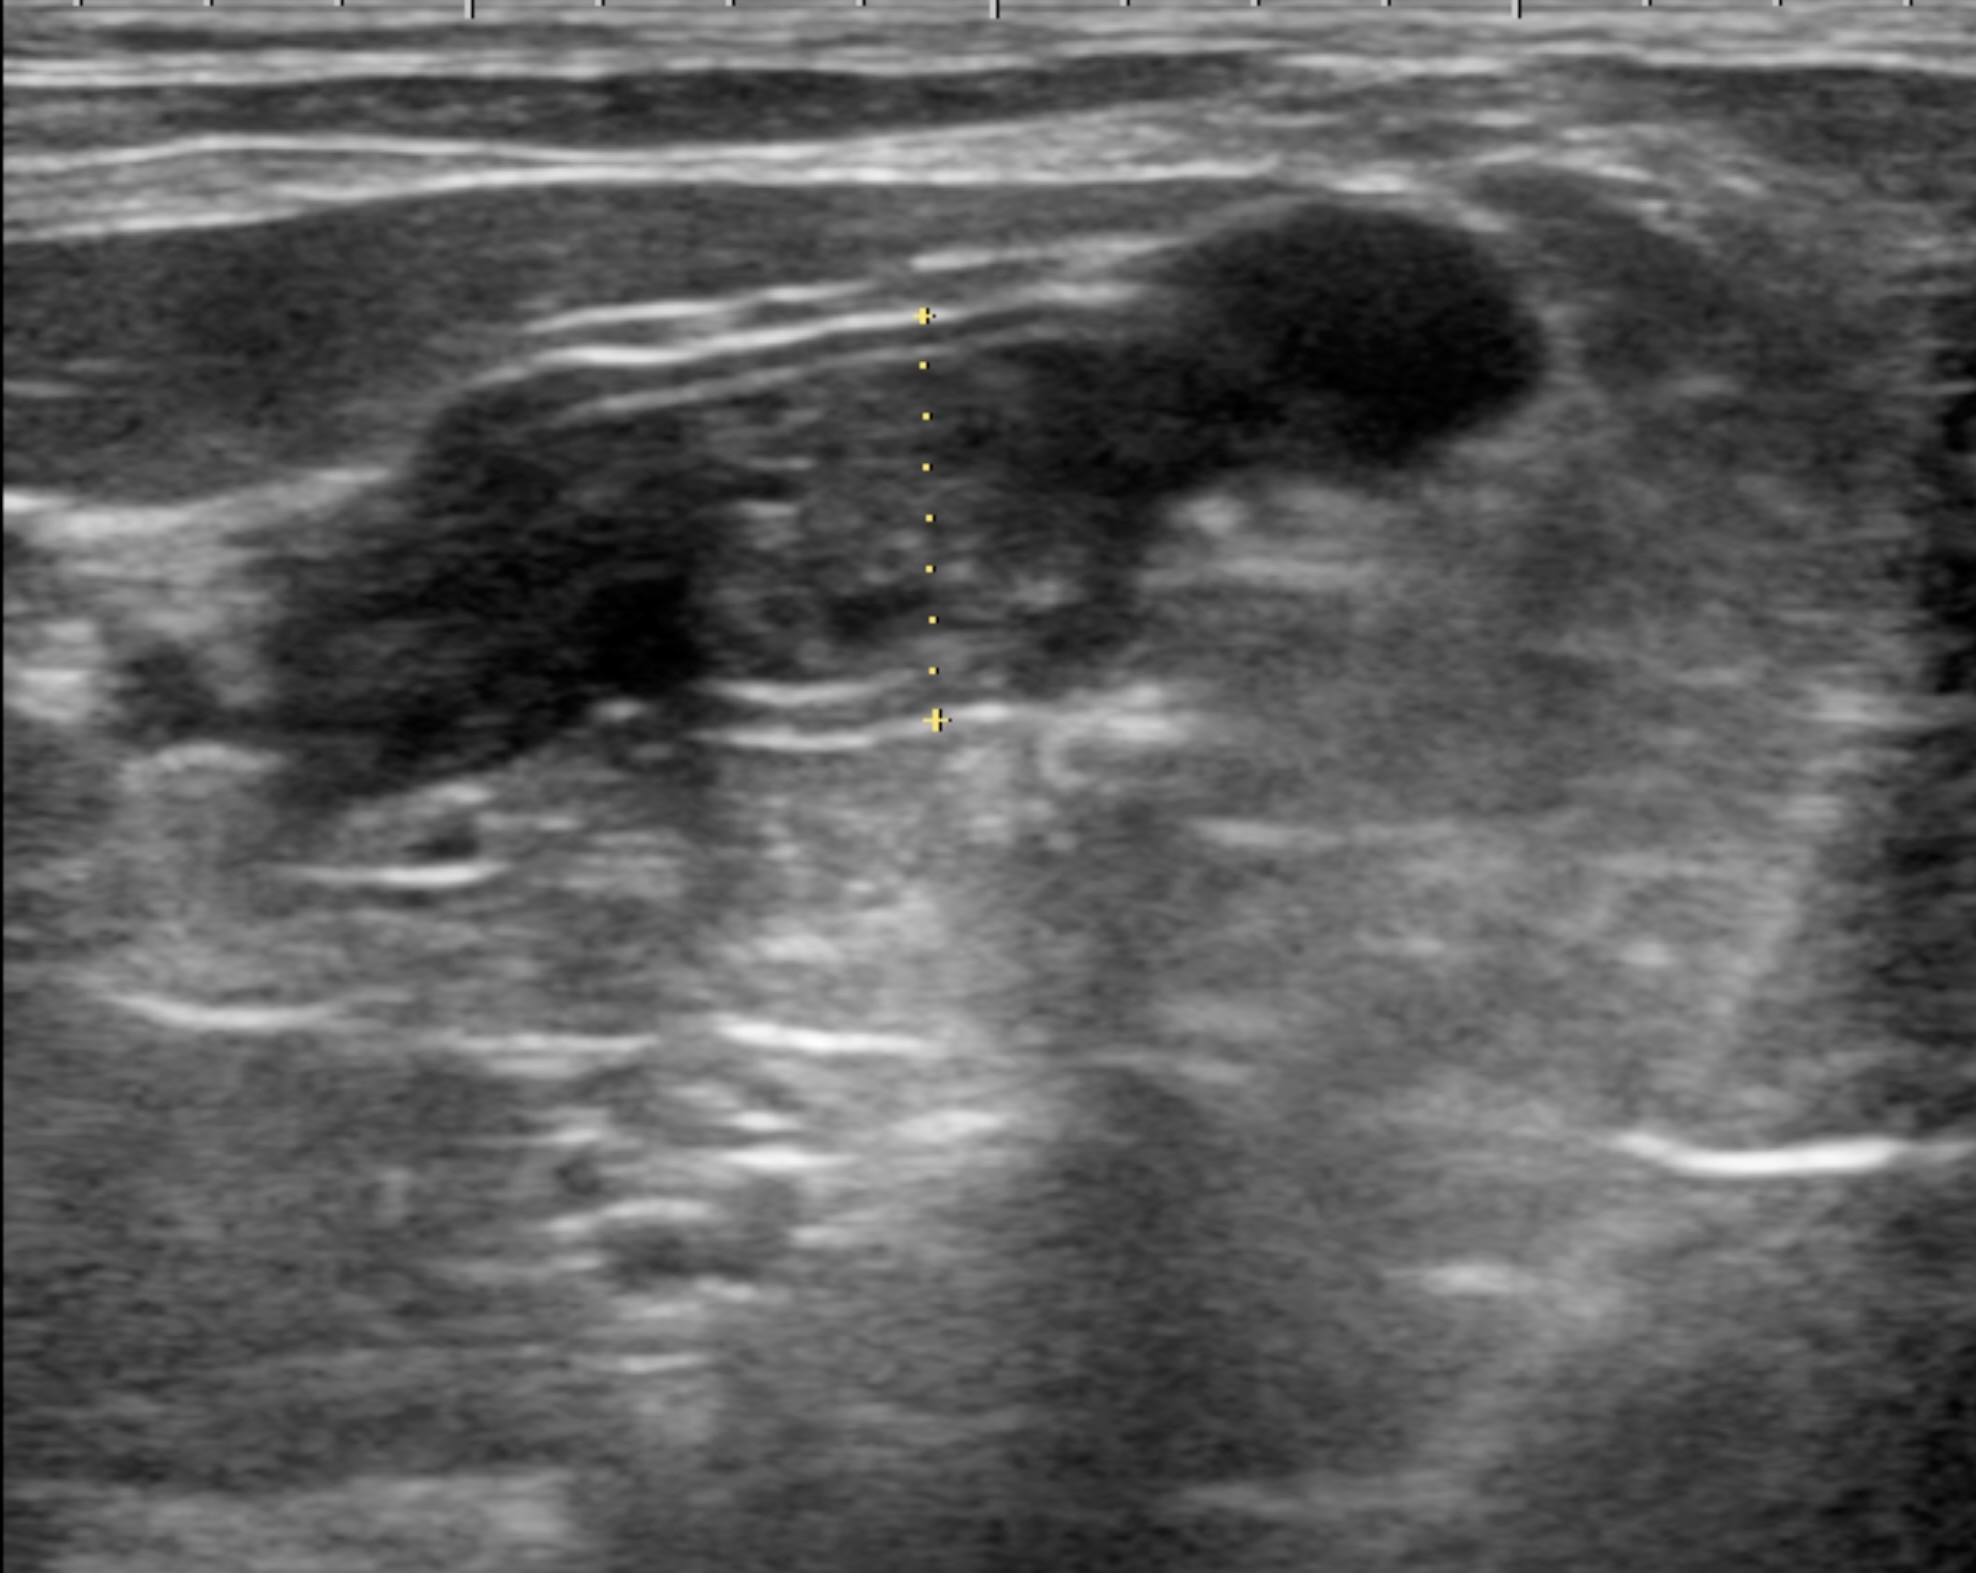

視診上、外傷などは認められず著変なし。超音波検査では子宮の軽度腫大が認められた。

子宮の縦断面